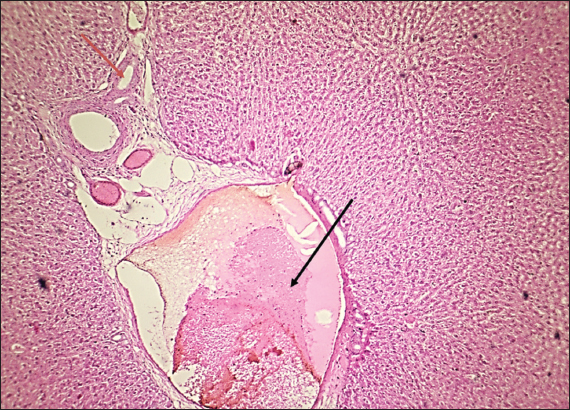

Fig. 2. Histological section of liver in rats drenched with 0.6 mg/kg citalopram and treated with 10 mg/kg J. regia pulp extract. The section shows the normal histological structure of hepatic tissue without any significant occupied lesion (H and E stain 100X).

Fig. 3. Histological section of liver in rats drenched with 0.6 mg/kg citalopram and treated with 20 mg/ kg J. regia pulp extract. The section shows the normal histological structure of hepatic tissue without any significant occupied lesion (H and E stain 100X).